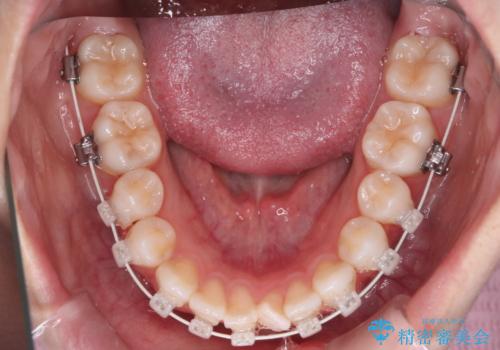

【審美装置】前歯で噛めない!抜歯しないで治したい

- 前歯の捻転とかみ合わせを主訴に来院されました。今回は抜歯をせずにIPRを実施し、並べる計画を立てました。

ワイヤー矯正を行いながら、顎間ゴムを患者さまにご協力していただき、短い期間で終了できました。